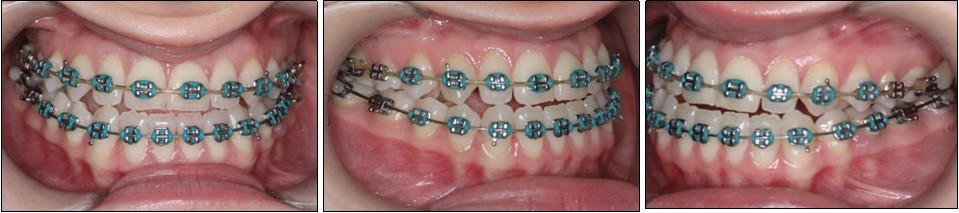

Firststage of treatment began with third molar odontectomies. Afterwards the patient was bonded with conventional straight-wire metallic orthodontic braces with an0.22’’ Roth slot.For patient confort the upper arch was bonded first, bonding of the lower arch following a month later. The archwire sequence was as follows: 0.012”, 0.014”, 0.016” NiTi archwires progressing to 0.016 × 0.016”, 0.016 × 0.022” and 0.019x0.025 NiTi archwires, ending with a 0.019x0.025 SS archwires.

The pre-surgical orthodontic preparation successfully met the following objectives: levelling and aligning, flattening of curbe of Spee, proclination of the lower incisors and elimination of dental compensations. Before surgery, the patient had a normal position of the lower incisors, with IMPA 88 degrees. (Figure 4) Before surgery, a slight anterior open bite and an anterior crossbite could be observed, due to the elimination of dental compensations. Crimpable hooks were placed between each tooth on the 0.019x0.025 SS archwires, to allow placement of intermaxillary elastics after surgery. (Figure 5).

Figure 5.Pre-surgical intraoral photographs

Pre-surgical intraoral photographs